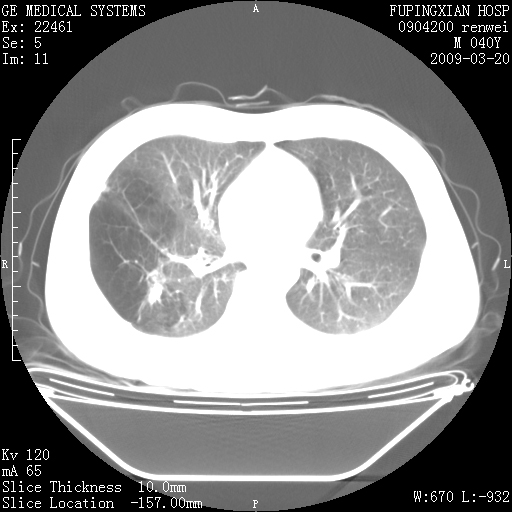

标题: CT18920:平时体健,体检时发现以下问题。 [打印本页]

标题: CT18920:平时体健,体检时发现以下问题。

单侧肺气肿表现,原因?   特发性或先天性可能

右肺气肿。

右肺局限性肺气肿

双肺弥漫磨玻样改变,肺纹理增重,考虑早期间质纤维化伴局部阻塞肺气肿,[考虑黏液栓]

透明肺

双肺弥漫磨玻样改变,右肺局限性肺气肿。病人没有症状?

考虑间质性肺炎伴右侧局限性肺气肿,

先天性支气管闭锁

右肺局限性肺气肿,原因?先天支气管闭锁?粘液栓?